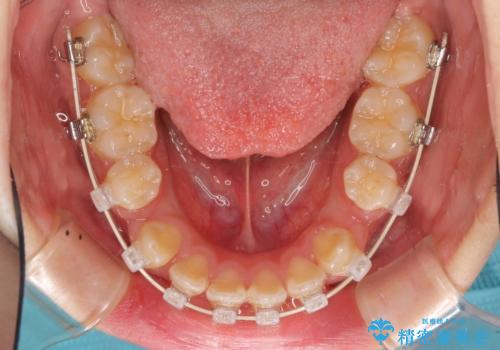

ハーフリンガル 半分裏側矯正による上下前突の抜歯矯正治療

- 矯正装置

- ハーフリンガル

- 上下左右4本の第1小臼歯を抜歯する、抜歯矯正を計画した。

抜歯矯正により前歯の位置が後ろに下がり、わずかではありますが、口元に改善がみられ、歯並びもきれいに整いました。